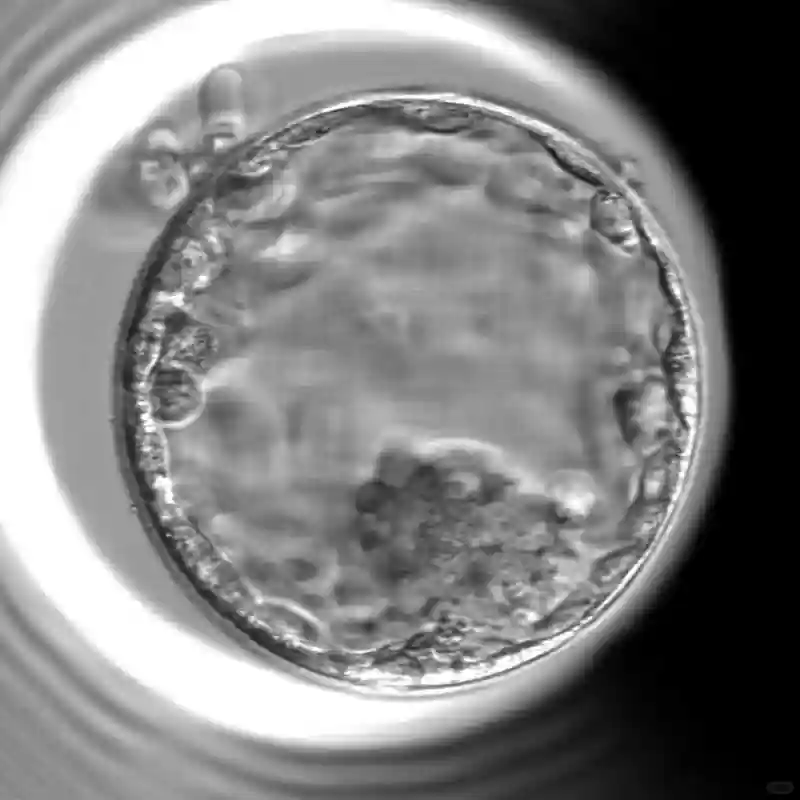

取卵后的第4天医院的胚胎学家给我打电话告诉我胚胎的情况。取了11颗卵子有10颗成功受精,到了第3天剩下8个胚胎,其中3个属于优等级、4个属于一般等级 和1个差等级。到了第6天我的胚胎就只剩下两个属于中上等级(1个是4BB 另一个是 5BA )其他的胚胎已停止成长。知道了这个消息有点小打击,11颗卵子到第六天居然只剩下2两个胚胎。 跟医院沟通后我决定再做一次促排卵,希望能取得更多优质的卵子增加怀孕的机会。我这次的两个胚胎会被冷冻起来,等第二次促排取卵后再连同第二次的胚胎一起做PGS 遗传基因检测筛查。#马来西亚试管婴儿##马来西亚医疗旅游# #马来西亚医疗#